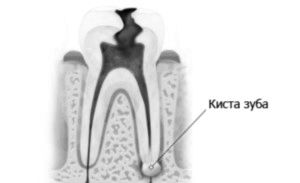

Кіста - невелика порожнина, заповнена рідиною, що утворюється у кореня зуба. Причиною виникнення запалення може бути інфекція самого зуба, порожнини рота або носоглотки. Також захворювання може бути наслідком травми. Ще недавно лікування обмежувалося видаленням хворого зуба, сучасна медицина пропонує і безопераційний метод: